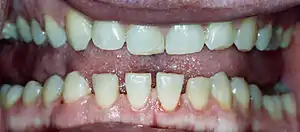

| Lower jaw showing the classic spacing of teeth due to acromegaly. | |

- Pronounced lower jaw protrusion (prognathism) with attendant macroglossia (enlargement of the tongue) and teeth spacing